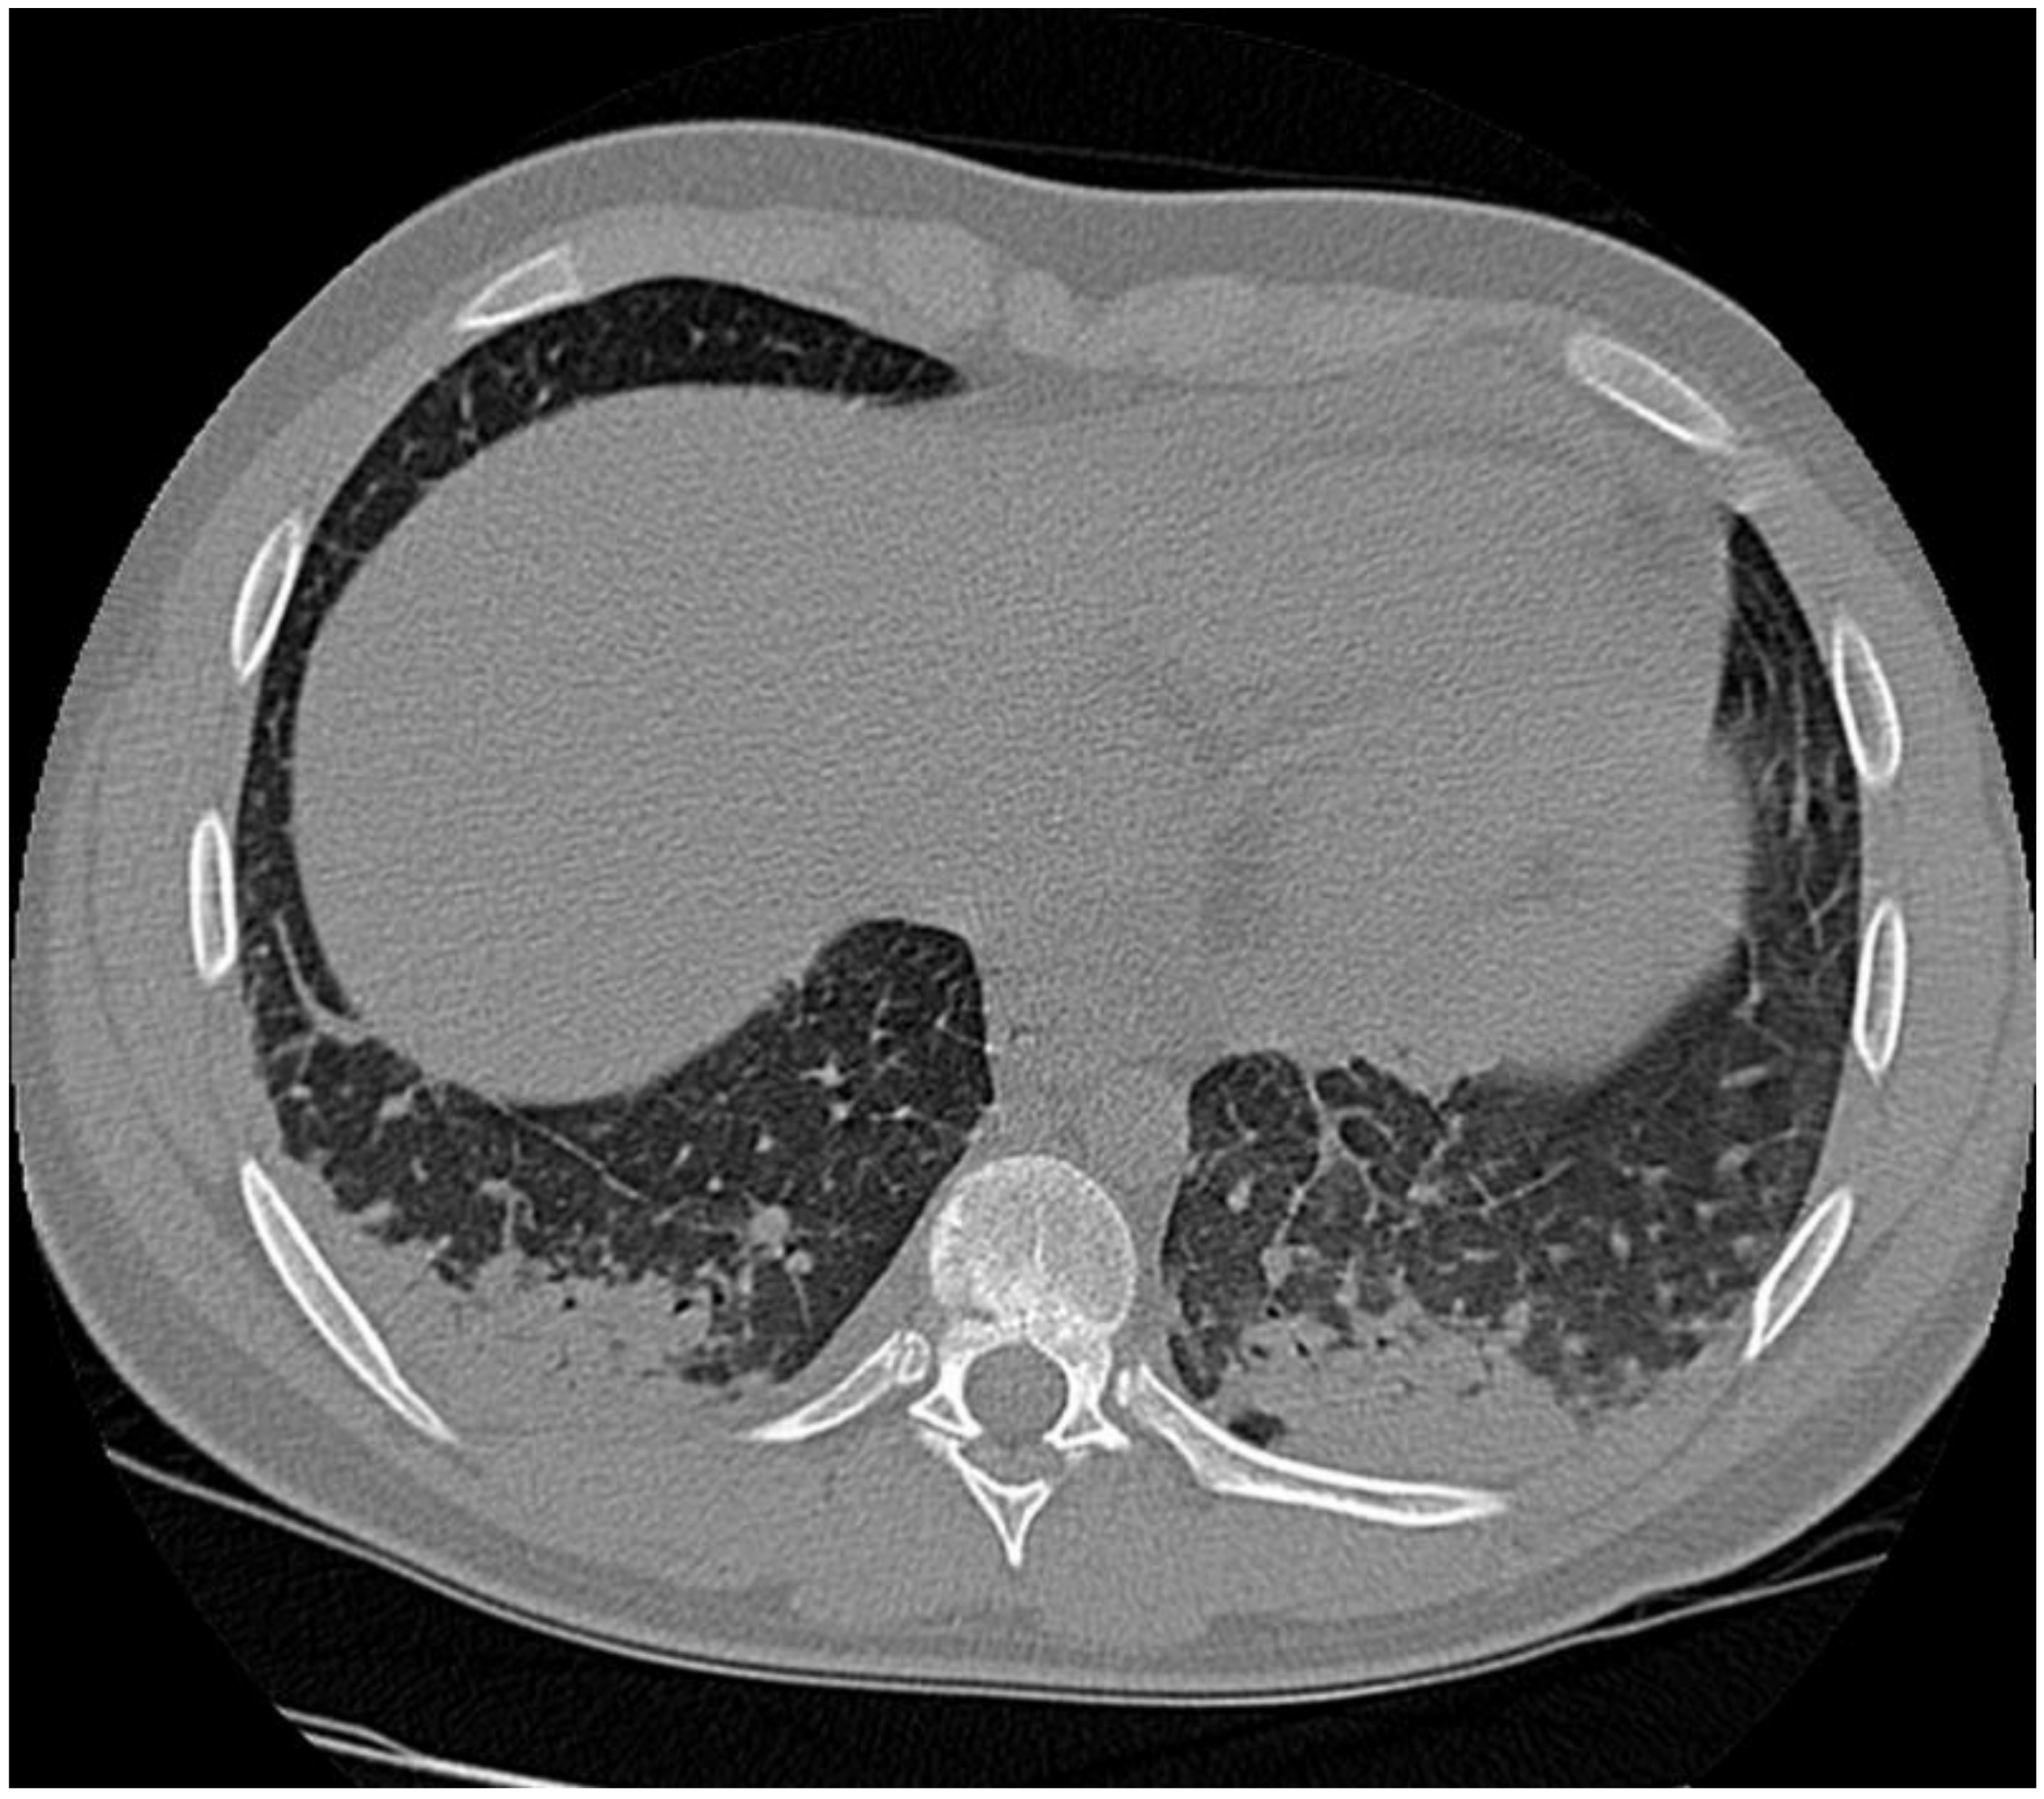

1.1. Case Presentation #1

1.2. Case Presentation #2